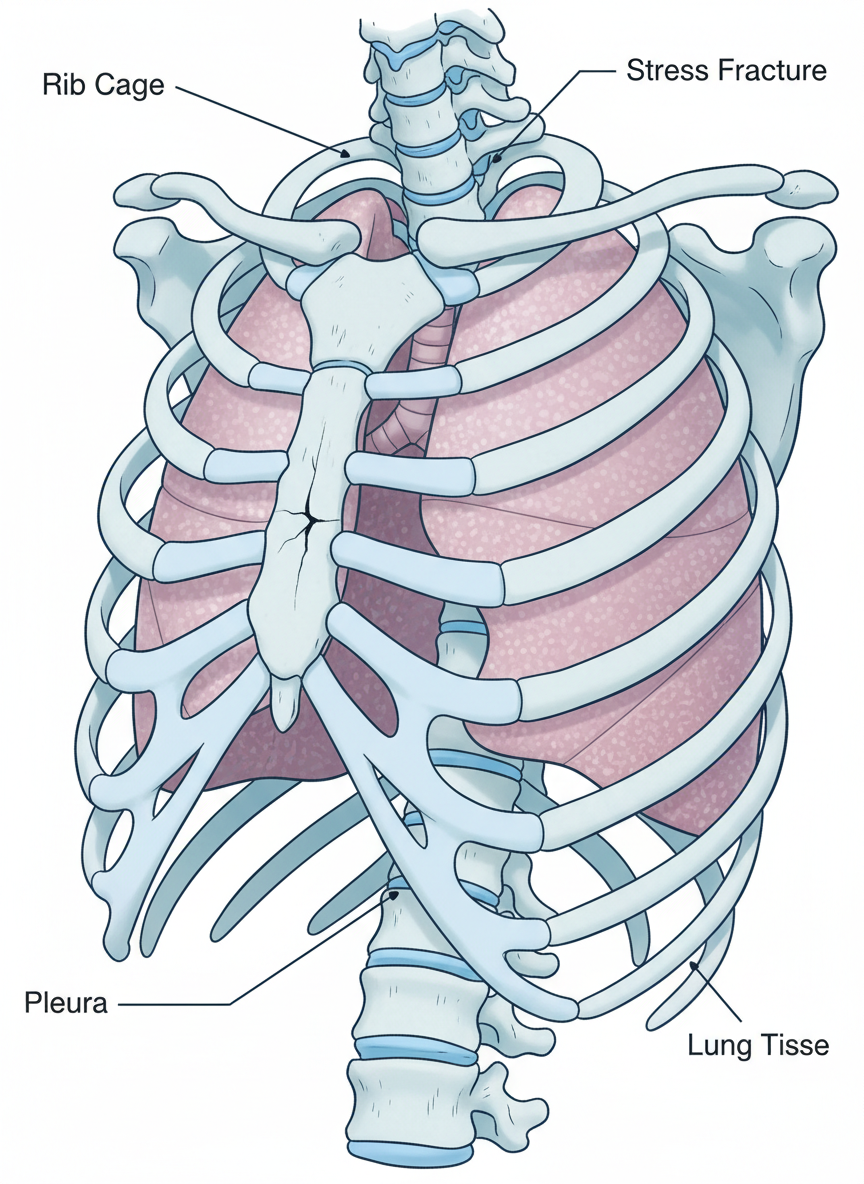

갈비뼈는 폐와 심장 등 중요한 장기를 보호하는 역할을 하는 만큼, 외부 충격에 취약할 수밖에 없어요. 사실 갈비뼈가 금이 가는 경우는 생각보다 흔하게 발생하는데요, 스포츠 활동 중 넘어지거나 부딪히는 경우, 교통사고, 낙상 등 직접적인 충격이 가장 흔한 원인이랍니다.

갈비뼈 골절 시 가장 걱정되는 것 중 하나가 폐렴 같은 합병증이에요. 통증 때문에 얕게 숨을 쉬다 보면 폐에 공기가 충분히 들어가지 못해 생길 수 있습니다. 따라서 통증이 허락하는 범위 내에서 주기적으로 심호흡 운동을 해주는 것이 필수적이에요.